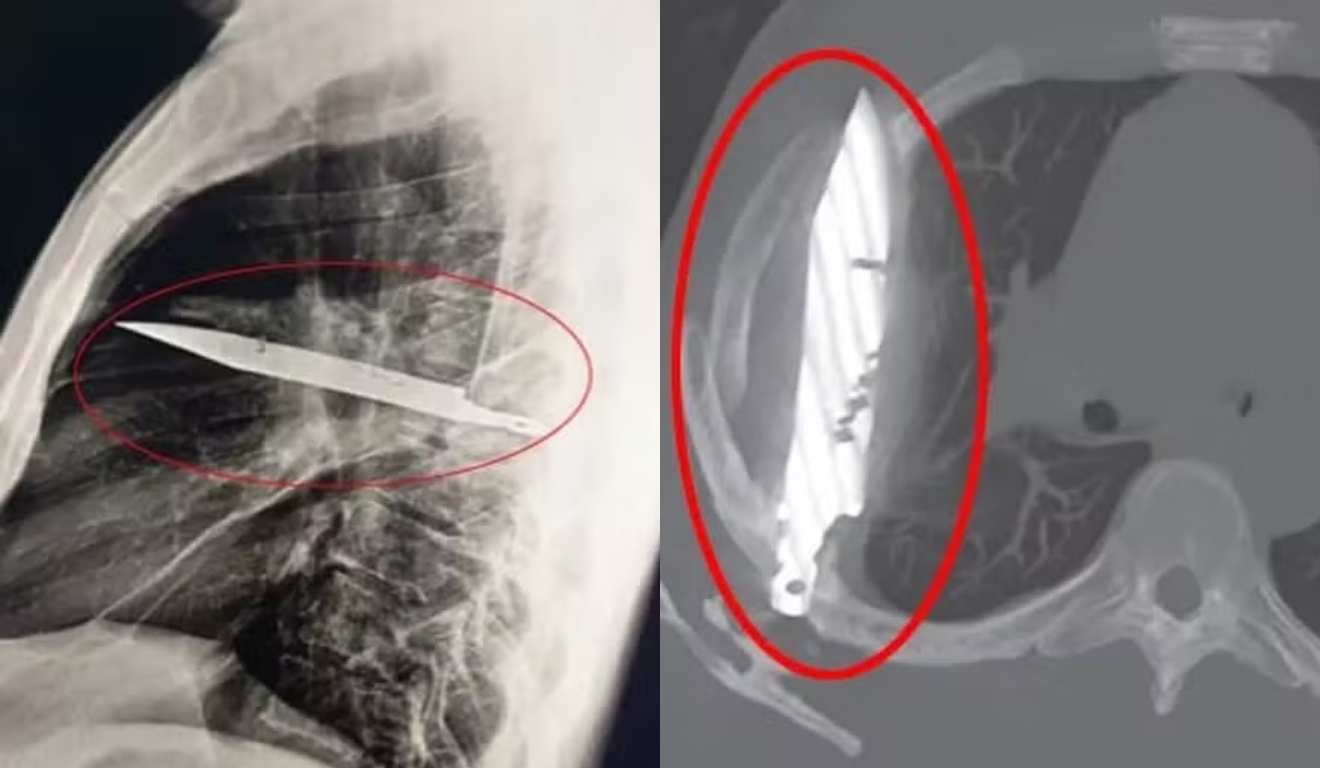

O mistério só foi solucionado com um exame de raio-x, que revelou a lâmina cravada na escápula direita do paciente, sem atingir órgãos vitais. A presença do metal explicava a secreção, resultado de tecido morto ao redor da lâmina.